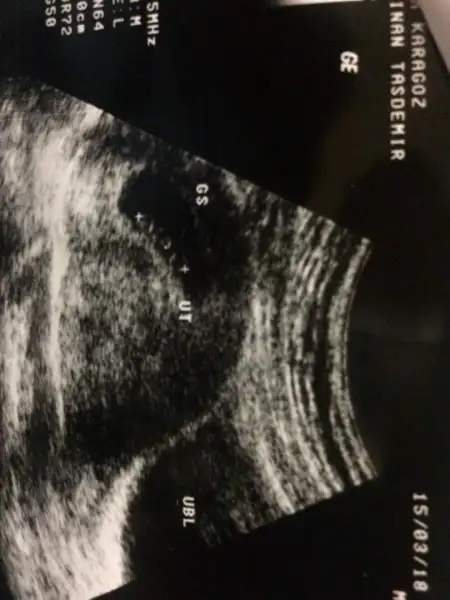

Merhaba arkadaşlar şimdi Dr geldik çok şükür herşey normal bugün 7+4 üm ama ultrasonda 8+1 çıktı 16.4 mm kalp atışı da var güzel haberler vermek istedim size :)

Bu da bebişim hadi kızlar bana cinsiyet tahmini yapalımEki Görüntüle 2124030